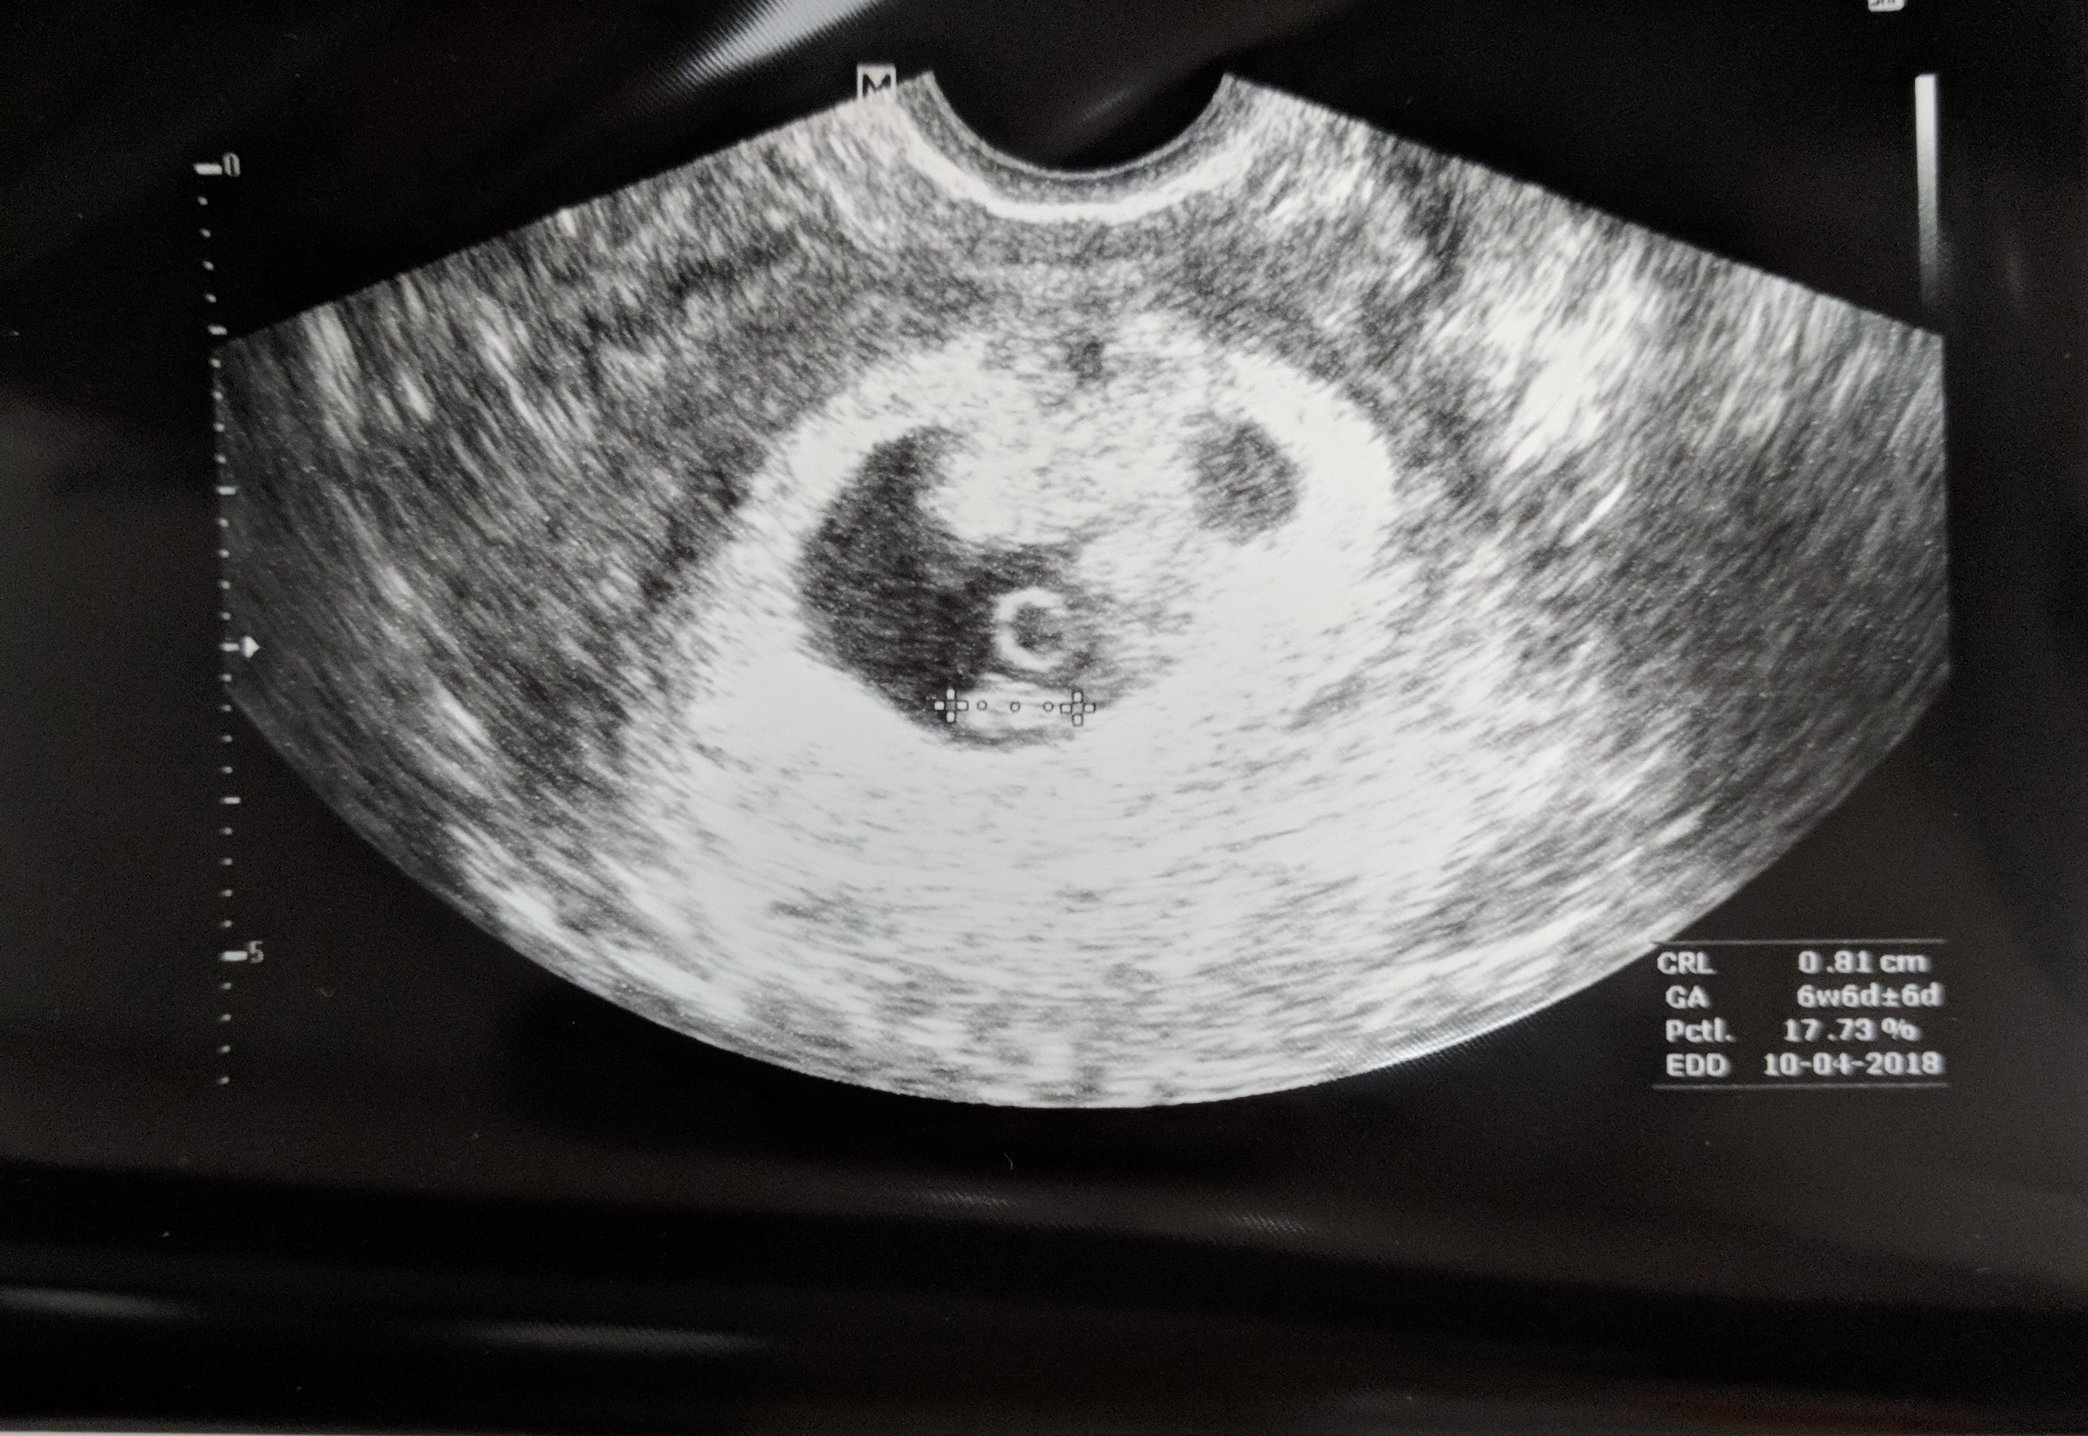

• Here is our little bean... Measuring 7 weeks (LMD is 7+3) but doc is keep DD at 9/30